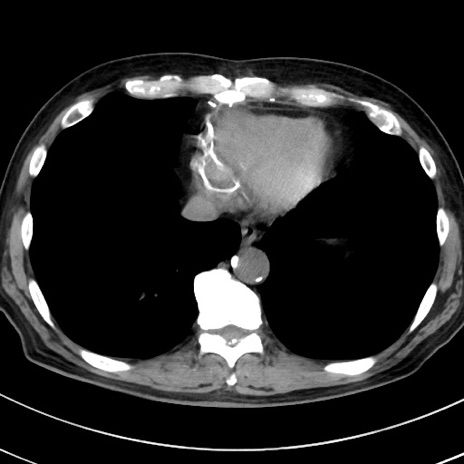

症例38(横断像)

【症例】70歳代 男性

【主訴】腹痛・嘔吐

【現病歴】昨晩より、嘔吐・腹痛あり。今朝になっても嘔吐あり。来院。

【既往歴】心臓バイパス手術、開腹胆摘、腸閉塞

【身体所見】BP 107/71mmHg、HR 116/min、腹部:平坦、軟、下腹部に軽度圧痛あり。反跳痛なし。

【データ】WBC 15100、CRP 0.32